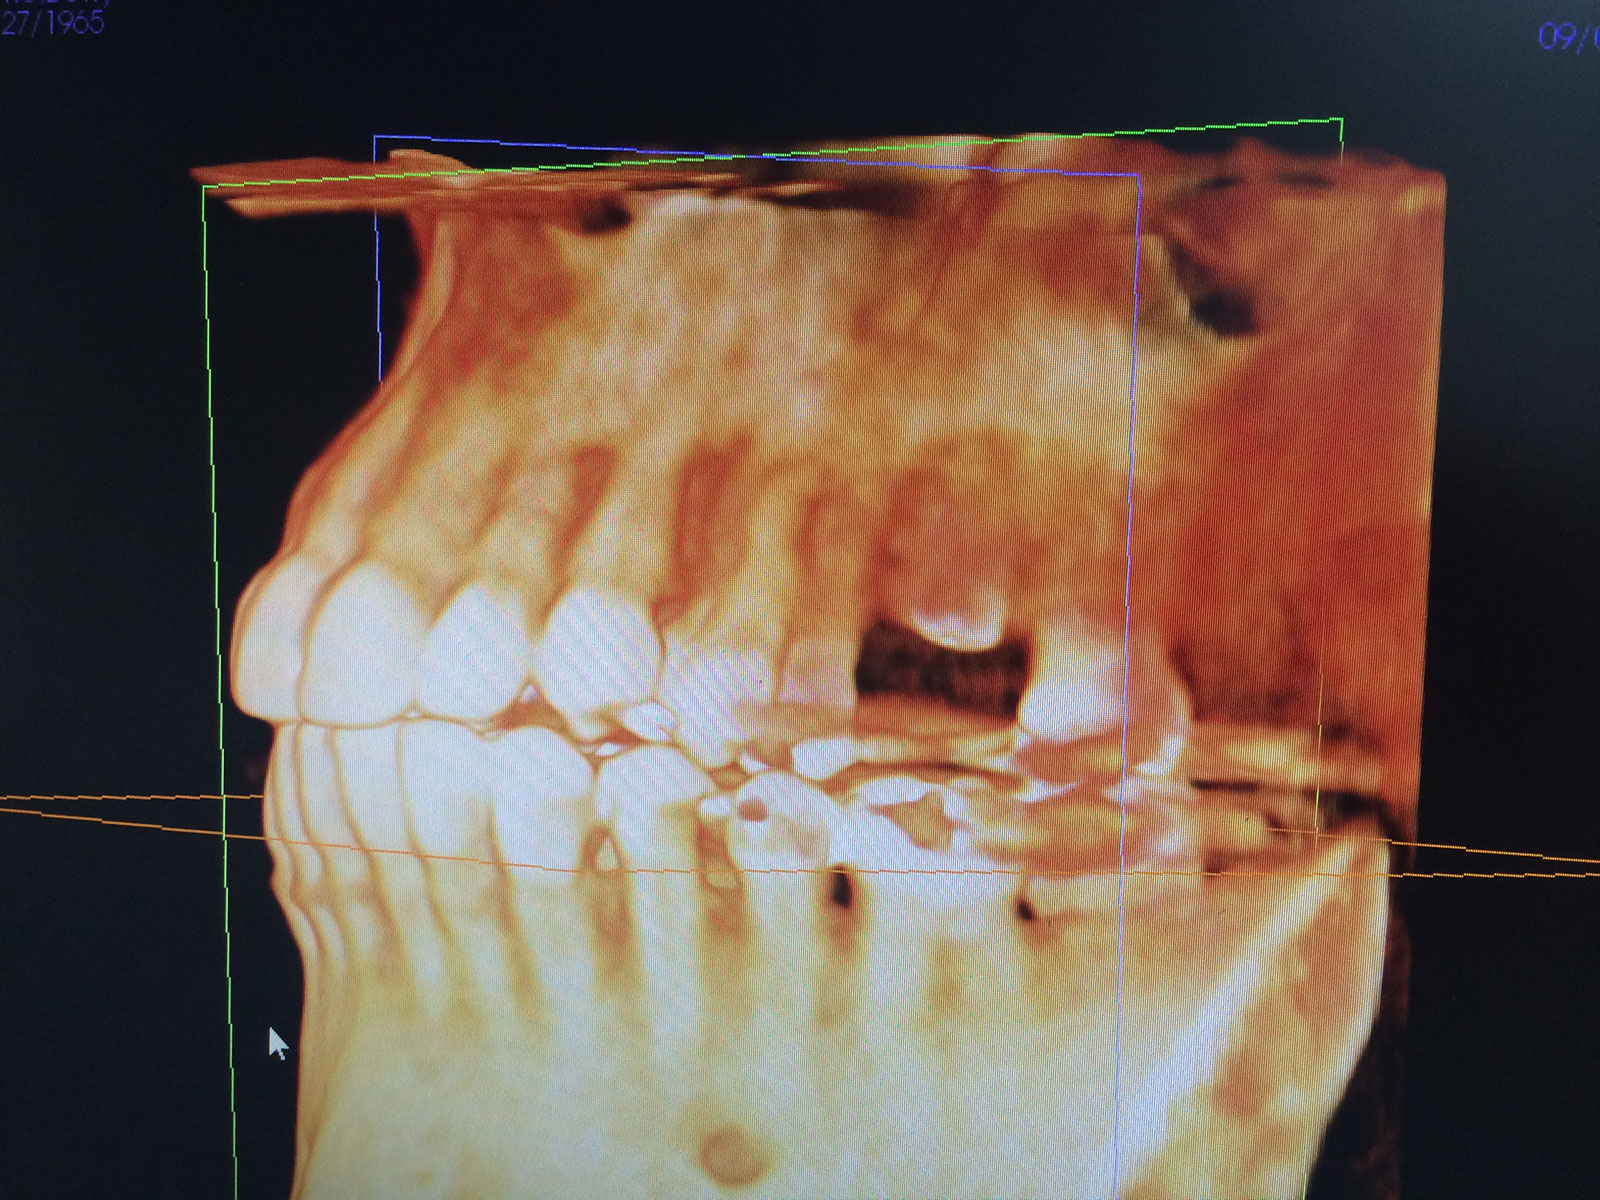

Sinus Grafting Procedures

A sinus grafting procedure, also known as a sinus augmentation, is for patients who have insufficient natural bone in the areas where dental implants are needed. They are long lasting, strong and sturdy, and fit and function like natural teeth. The procedure involves adding bone, either your own natural bone from another part of the body, from a donor or made of processed or synthetic bone material, and placing it below the sinus so that the implants can be placed. After the bone has healed and developed, usually around four to 12 months, the dental implants can be placed.

The photos on this website are from real surgeries performed by Dr. Ulloa. Due to the

graphic nature of the images and content, viewer discretion is advised.

Click to enlarge images